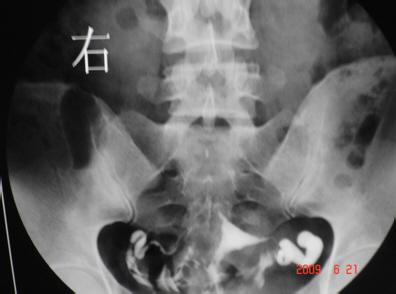

弱精症结果提示:双侧输卵管通而不畅子宫输卵管造影和宫腔镜检查

图片尺寸582x409